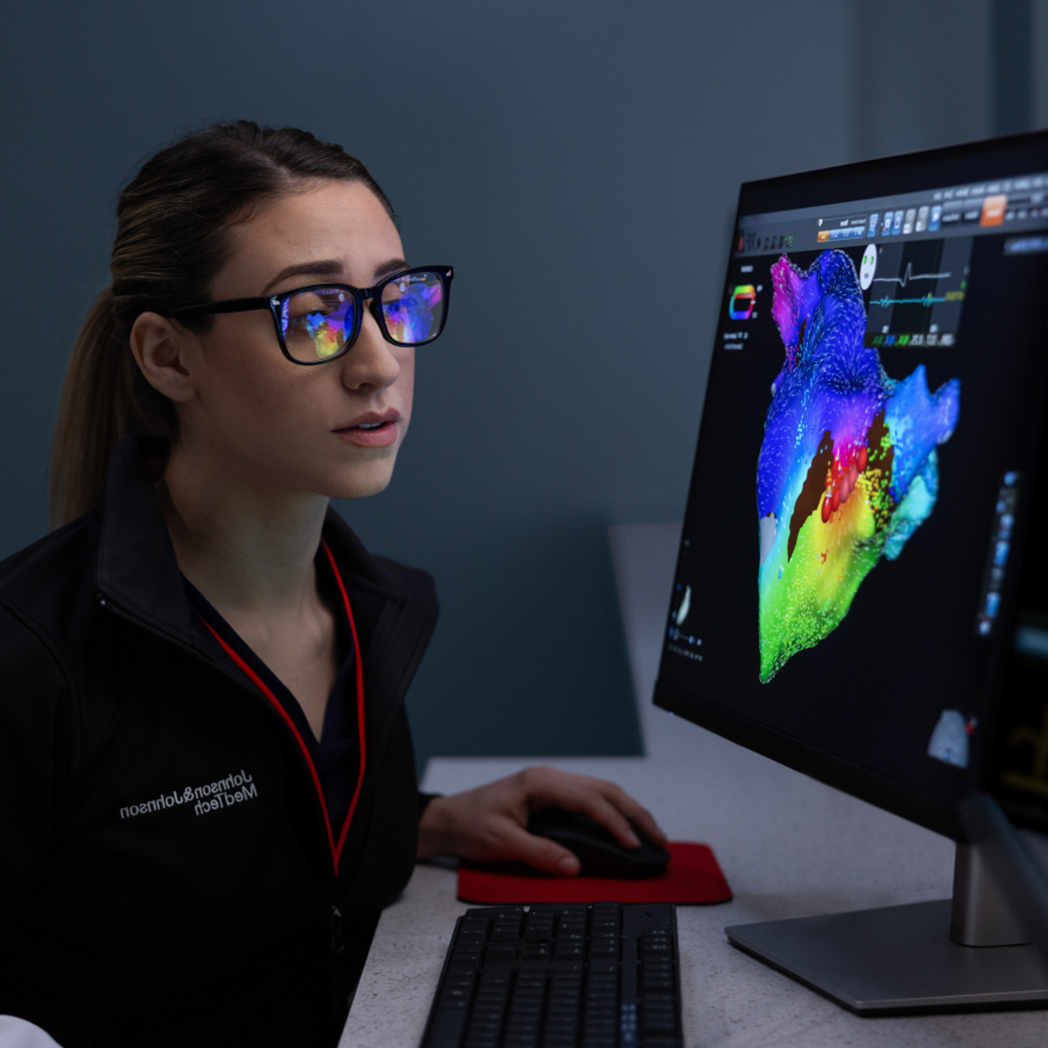

Gain valuable experience in clinical settings, support physicians during cardiac ablation procedures and build your skills to advance within our Associate Clinical Account Specialist (ACAS) and Clinical Account Specialist (CAS) pathways. You’ll help patients with cardiac arrhythmia live the lives they want by delivering breakthrough medtech innovation. You can expect to build trusted partnerships with physicians, electrophysiologists, electrophysiology lab teams and other innovators.

Clinical Account Specialist (CAS) role

Already have experience in EP? Accelerate your career with the global market leader in the science and technology of cardiac arrhythmia treatment. Our clinical account specialist (CAS) program is designed for experienced EP professionals who want to take their careers to the next level. As a Clinical Account Specialist, you can provide expert clinical product and technical assistance and training to physicians and EP lab staff on the effective use of electrophysiology systems and catheter equipment during case procedures.

- Ability to maintain advanced clinical knowledge of cardiac ablation and cardiac imaging, technical knowledge of EP technology, advancements, and the business landscape

- Ability to maintain advanced clinical knowledge of cardiac ablation and cardiac imaging, technical knowledge of EP technology, advancements, and the business landscape